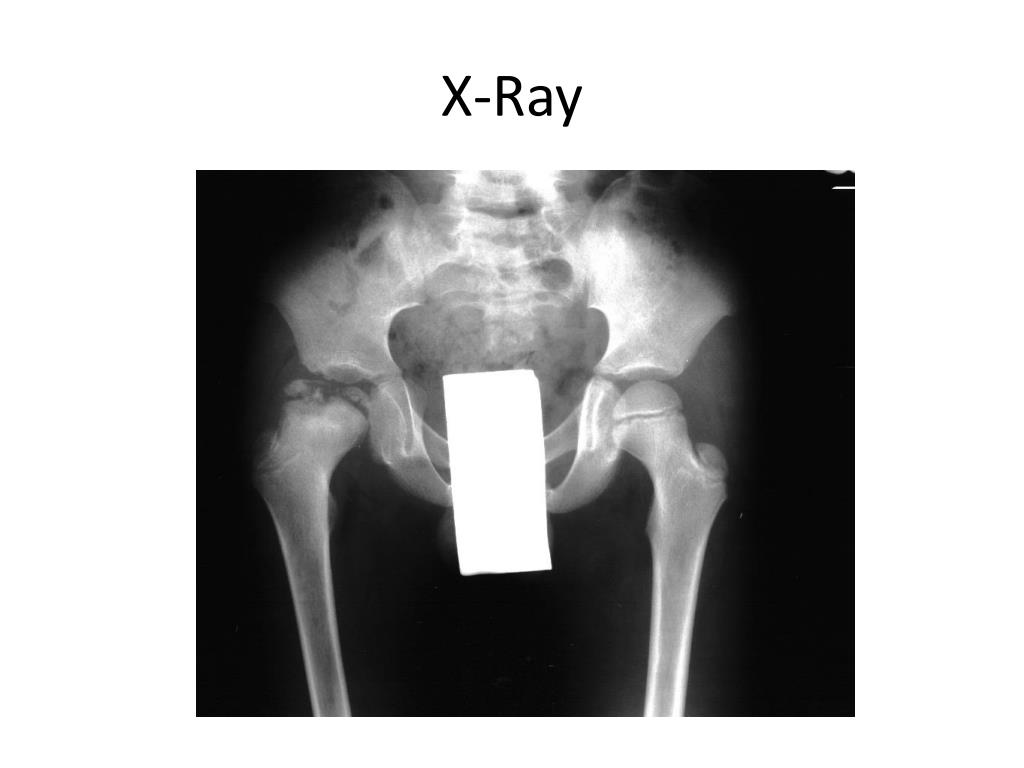

17. X-Ray

15. Imaging Evaluation

16. Imaging Evaluation

18. Imaging Evaluation • MRI • Bone scan • Arthrography • X-ray